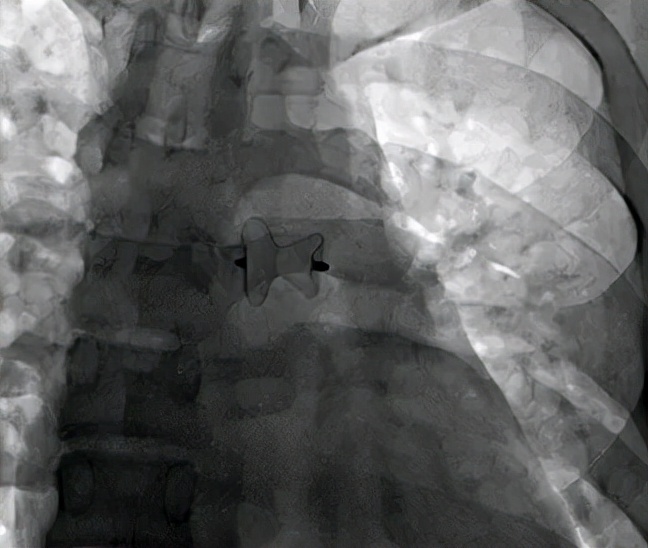

封堵器释放后形态。缺损位置高,位于升主动脉接近主动脉弓处,释放后封堵器形态良好。